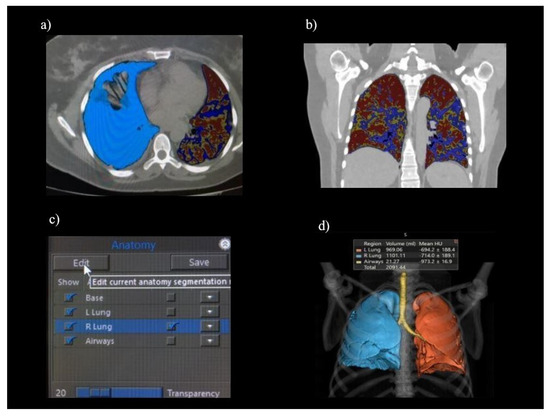

2.3. Image Analysis

- -